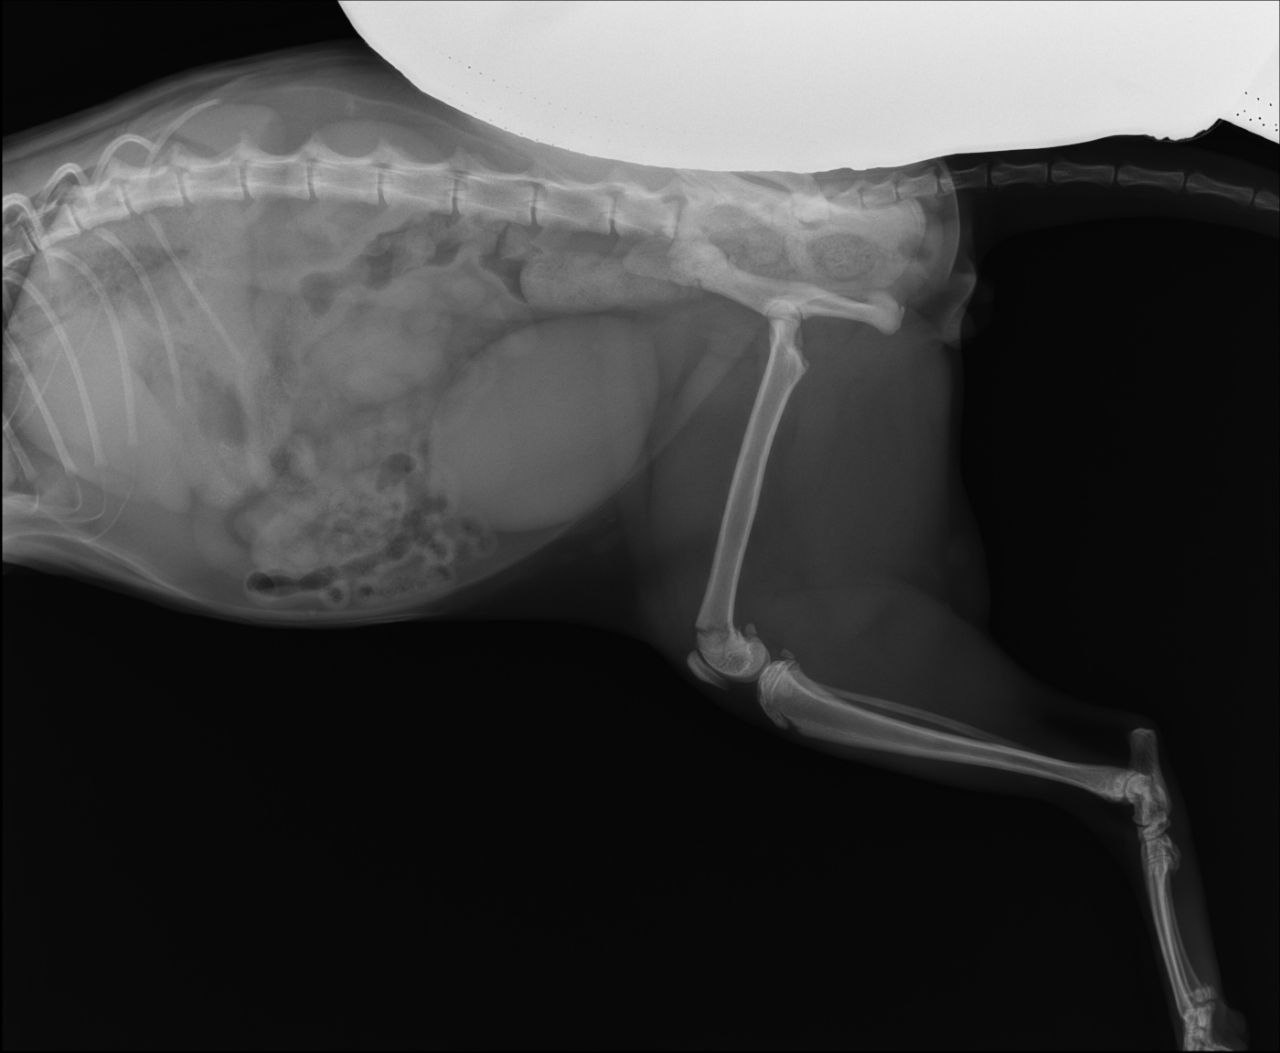

Перелом бедренной кости, требуется операция. В остальном здоров и бодр, ест, пьёт, ходит в туалет.

Тут закрытый перелом не кости а коленного сустава, сильно выраженная бронхиальная картина. Антибиотик нужен

Он писает? На снимке мочевой как дыня переполнен

Сёму прооперировали, теперь щеголяет бритой ногой, внутри которой крутые спицы. Отойдя от наркоза, стал бодр и ласков, как всегда, и уже на передержке.